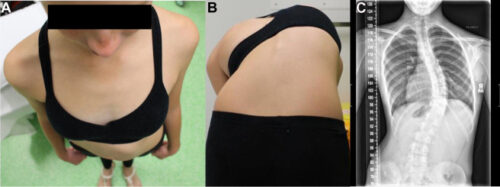

تشخيص الجنف في مراحله المبكرة ليس أمرًا سهلاً. في البداية، قد لا يظهر الانحناء بوضوح، خاصة إذا كان بسيطًا. غالبًا يتم اكتشاف الحالة عندما يزداد الانحناء ليؤثر على شكل الجسم أو وضعية الأكتاف والحوض. ولهذا السبب قد تمر سنوات قبل أن يعرف الأهل أن طفلهم مصاب بالجنف.

كيف تكتشف اعوجاج العمود الفقري مبكرًا عند طفلك؟

من المهم أن يكون الأهل على وعي بالعلامات المبكرة، ومنها:

تفاوت في مستوى الأكتاف.

بروز أحد جانبي الصدر أكثر من الآخر.

ميل الجسم إلى أحد الجانبين.

عدم تساوي الخصر أو الوركين.

في حال ملاحظة أي من هذه العلامات، يجب استشارة الطبيب على الفور لعمل فحص سريري وتصوير بالأشعة إذا لزم الأمر.